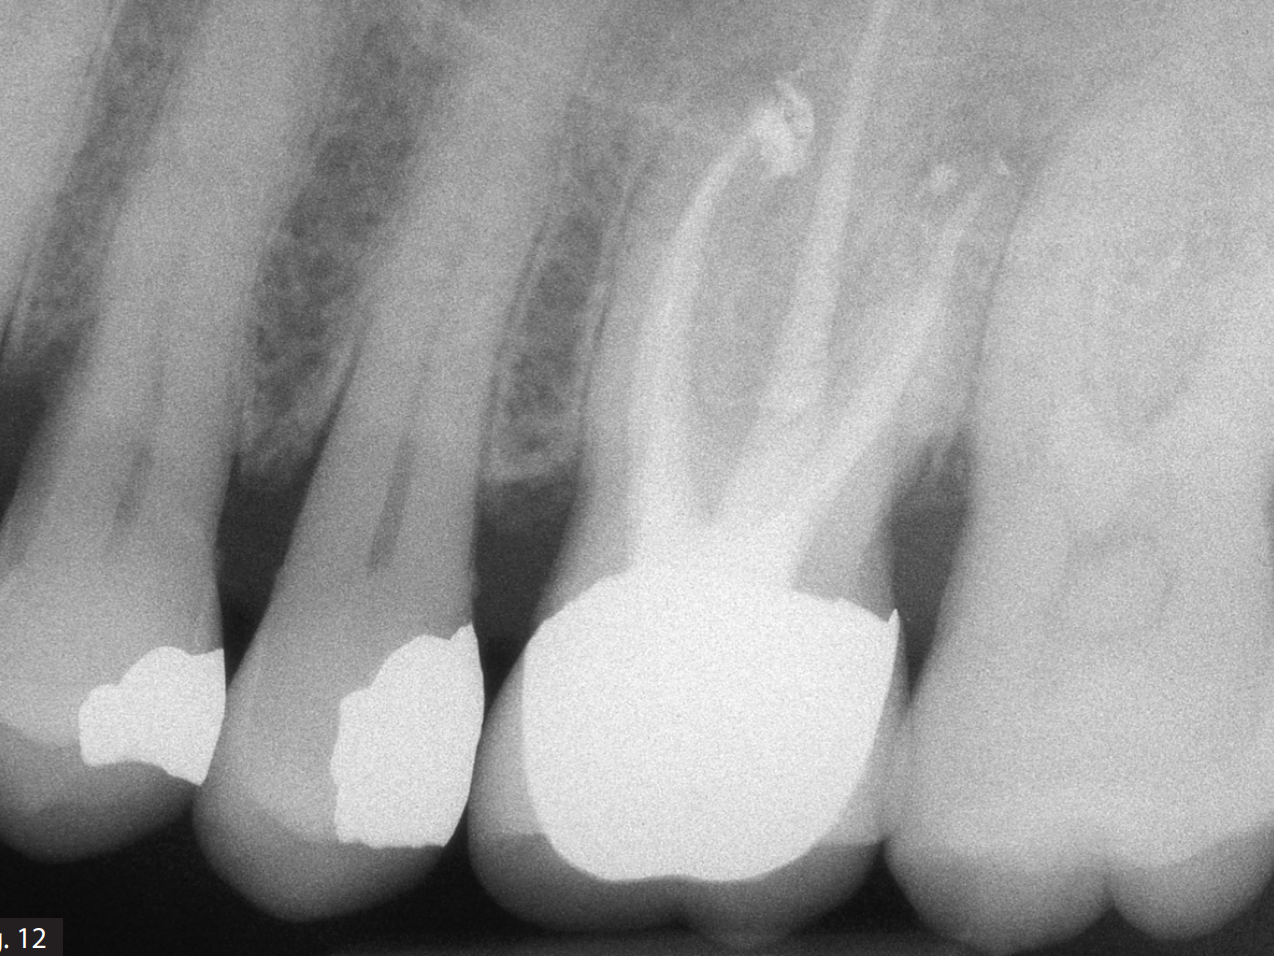

1. Enhanced Debris Removal – Mechanical instrumentation alone cannot fully clean the intricate anatomy of the root canal system. Irrigation solutions help clean out dentin debris, pulp tissue, and bacteria from areas that instruments cannot reach.

3. Dissolution of Organic and Inorganic Matter – Some solutions can break down necrotic tissue and smear layers, improving the penetration of medicaments and sealers.

5. Improved Success Rate – Proper irrigation significantly enhances the chances of long-term success by reducing bacterial load and ensuring a cleaner environment for sealing the root canal.